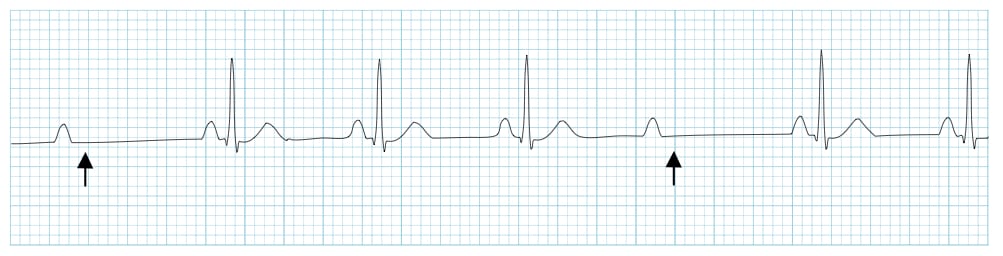

ECG Example – U Wave

Note that there is a positive deflection (arrowed) after the T wave, and before the next P wave, that is the U wave.

© Life in the Fast Lane. Licensed under CC BY-NC 4.0